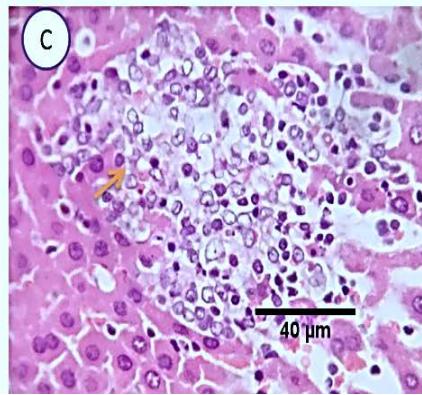

Liver: Examined sections from liver of this group denoted moderate portal biliary proliferation, congestion of portal blood vessels, round cell infiltration, multifocal interstitial lymphocytic and macrophages aggregations replacing previous necrotic patches beside degenerative changes in a few hepatocytes.(Fig.7).

Fig. 5: Photo-micrograph from liver, group (3), showing, portal biliary proliferation (yellow arrow), congestions of portal blood vessels (black arrow) and round cell infiltration and interstitial lymphocytic and macro-phages aggregations replacing previous necrotic patches (orange arrow). Scale bars 120, 40, 40 um.